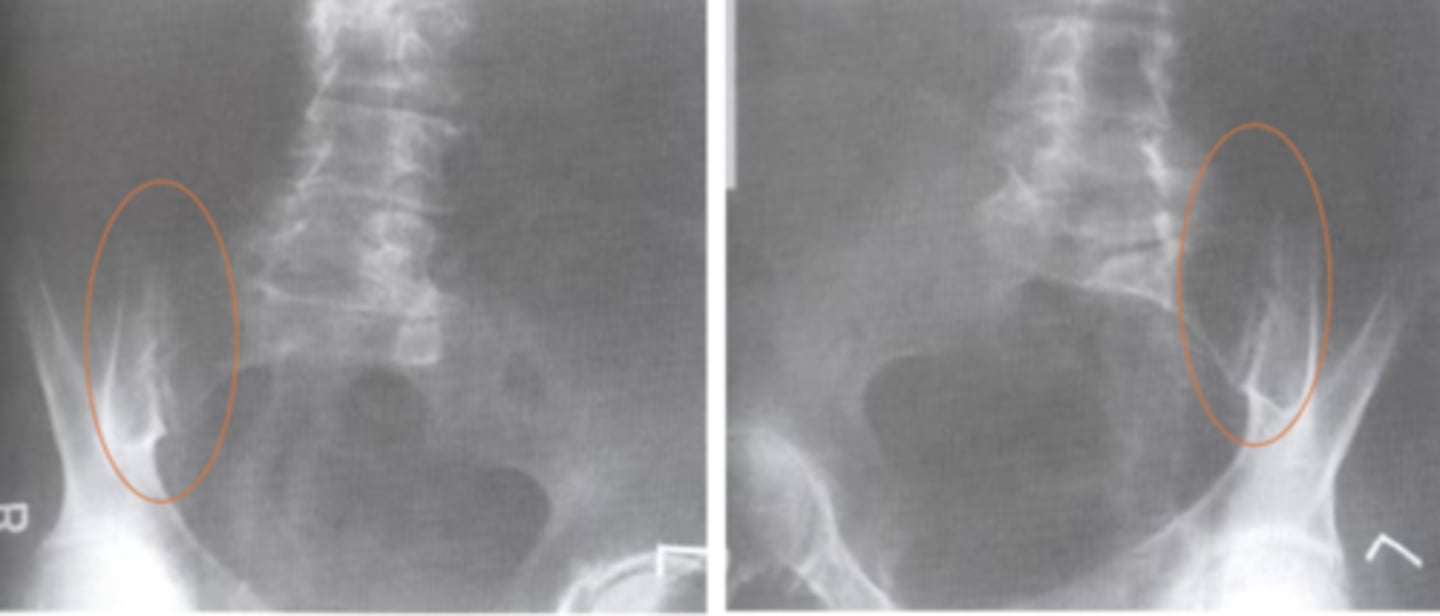

Spondylolysis

What is the issue?

ankylosing spondylitis